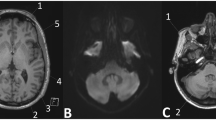

In patients with RRMS, SI within the dentate nucleus and globus pallidus increased on unenhanced T1-weighted images after multiple gadobutrol injections. Administration of the same total amount of gadobutrol over a shorter period caused greater SI increase.

• Gadolinium deposition may occur within the human brain after multiple gadolinium contrast administrations

• Increasing T1W signal intensity occurs within the dentate nucleus and globus pallidus

• Increasing signal intensity may be a consequence of multiple administrations of gadobutrol

• Administration of gadobutrol over a shorter period causes greater signal intensity increase